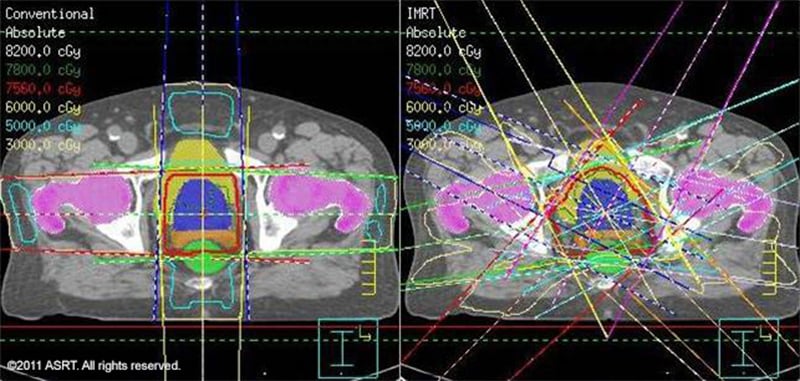

Radiation therapy is the primary tool to target tumors inside patients’ bodies. As the radiation strikes human tissue, it produces highly energized ions that gradually shrink and destroy the nucleus of malignant tumor cells. However, it’s targeted so it doesn’t damage the surrounding tissue.

Radiation Therapy / Image © ASRT

Radiation therapy

Image © ASRT